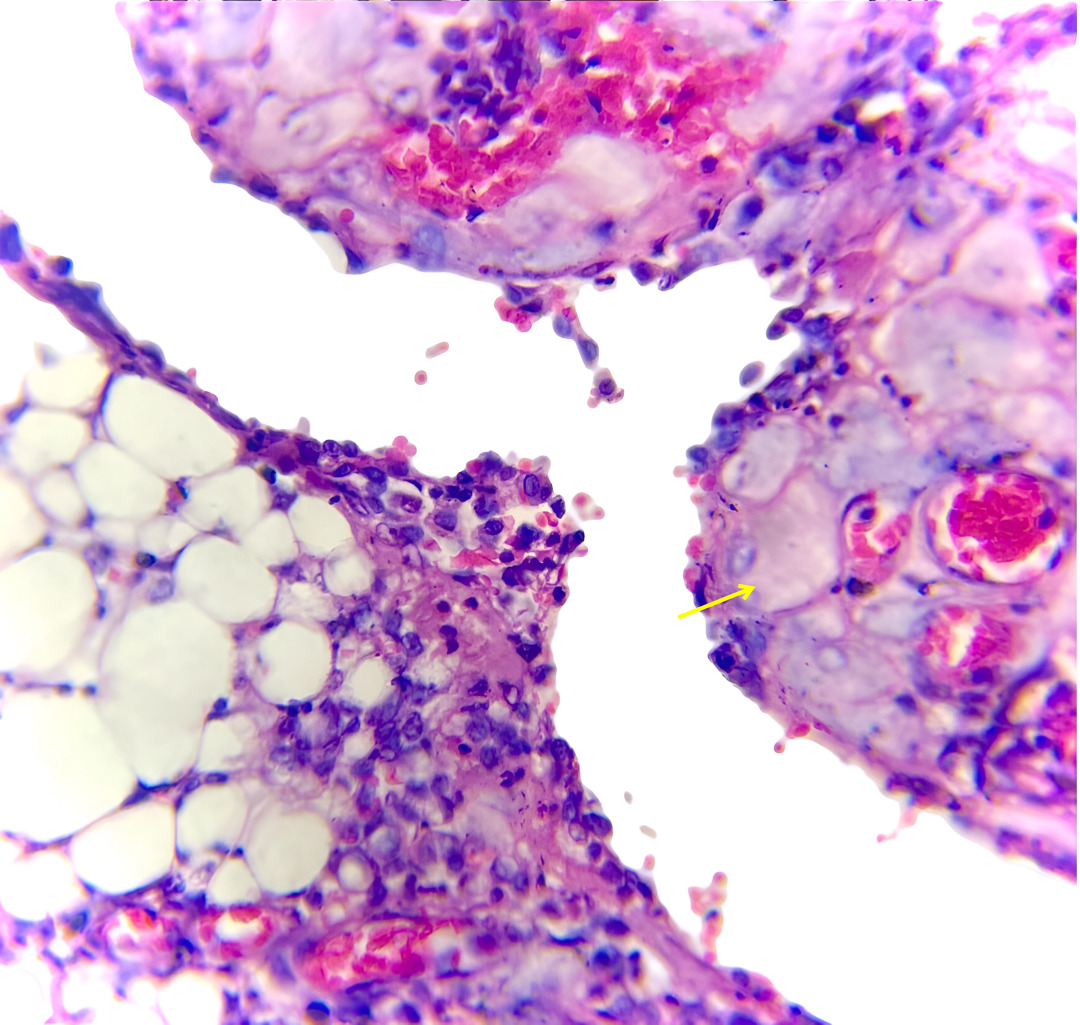

Case presentation: We report a case of a 29-year-old woman who underwent caesarean section, during which multiple nodular deposits were incidentally observed on the omentum. These lesions were initially suspected to represent metastatic disease. The patient was otherwise asymptomatic, with no significant medical or surgical history. Histopathological examination revealed sheets of large polygonal cells with abundant eosinophilic cytoplasm and no evidence of atypia or mitotic activity, confirming the diagnosis of omental deciduosis.

Discussion: Omental deciduosis, though uncommon, is most often associated with pregnancy and usually regresses spontaneously in the postpartum period. Its clinical importance lies in its close resemblance to conditions such as peritoneal carcinomatosis, tuberculous peritonitis, or deciduoid mesothelioma. Frozen section and immunohistochemistry may aid in difficult cases, but in most instances, routine histopathology is sufficient for diagnosis. Awareness of this entity among both surgeons and pathologists is crucial to prevent misinterpretation and avoid unnecessary aggressive interventions.

Conclusion: Omental deciduosis is a rare but benign condition that can mimic serious intra-abdominal pathology. Recognition of its characteristic histopathological features ensures accurate diagnosis and helps prevent overtreatment.